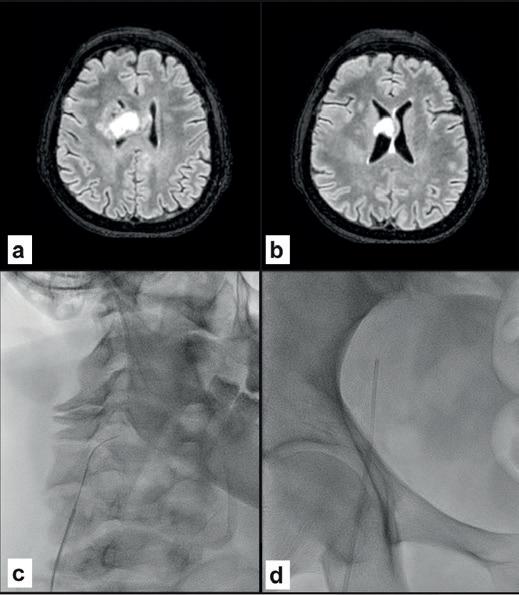

TWO

Female 60 years old

High-grade right frontal glioblastoma extending to the corpus callosum (A, B). Surgical histological confirmation but with negative tissue-based molecular testing. Pre-operative liquid biopsy from the right jugular vein (C) showing BRAF and PIK3CA mutations. Negative peripheral sample (D).

where venous sampling provides more effective molecular characterisation than peripheral sampling.

Radiosurgery is increasingly used in cancer treatment, sometimes as the only option, with a consensus for its use in the absence of histological examination. Liquid biopsy can confirm the diagnosis and assess treatment response or resistance during follow-up. A liquid biopsy showing a mutation consistent with glial neoplasm (Case two) is decisive not only when histological diagnosis is not possible but also for monitoring treatment in the event of recurrence or progression. Molecular diagnosis has a higher success rate on cerebrospinal fluid than on peripheral blood but repeated lumbar puncture is not without risk for the patient. Retrograde percutaneous catheterisation of the jugular veins is an outpatient procedure known since its use in the diagnosis of pituitary tumours.